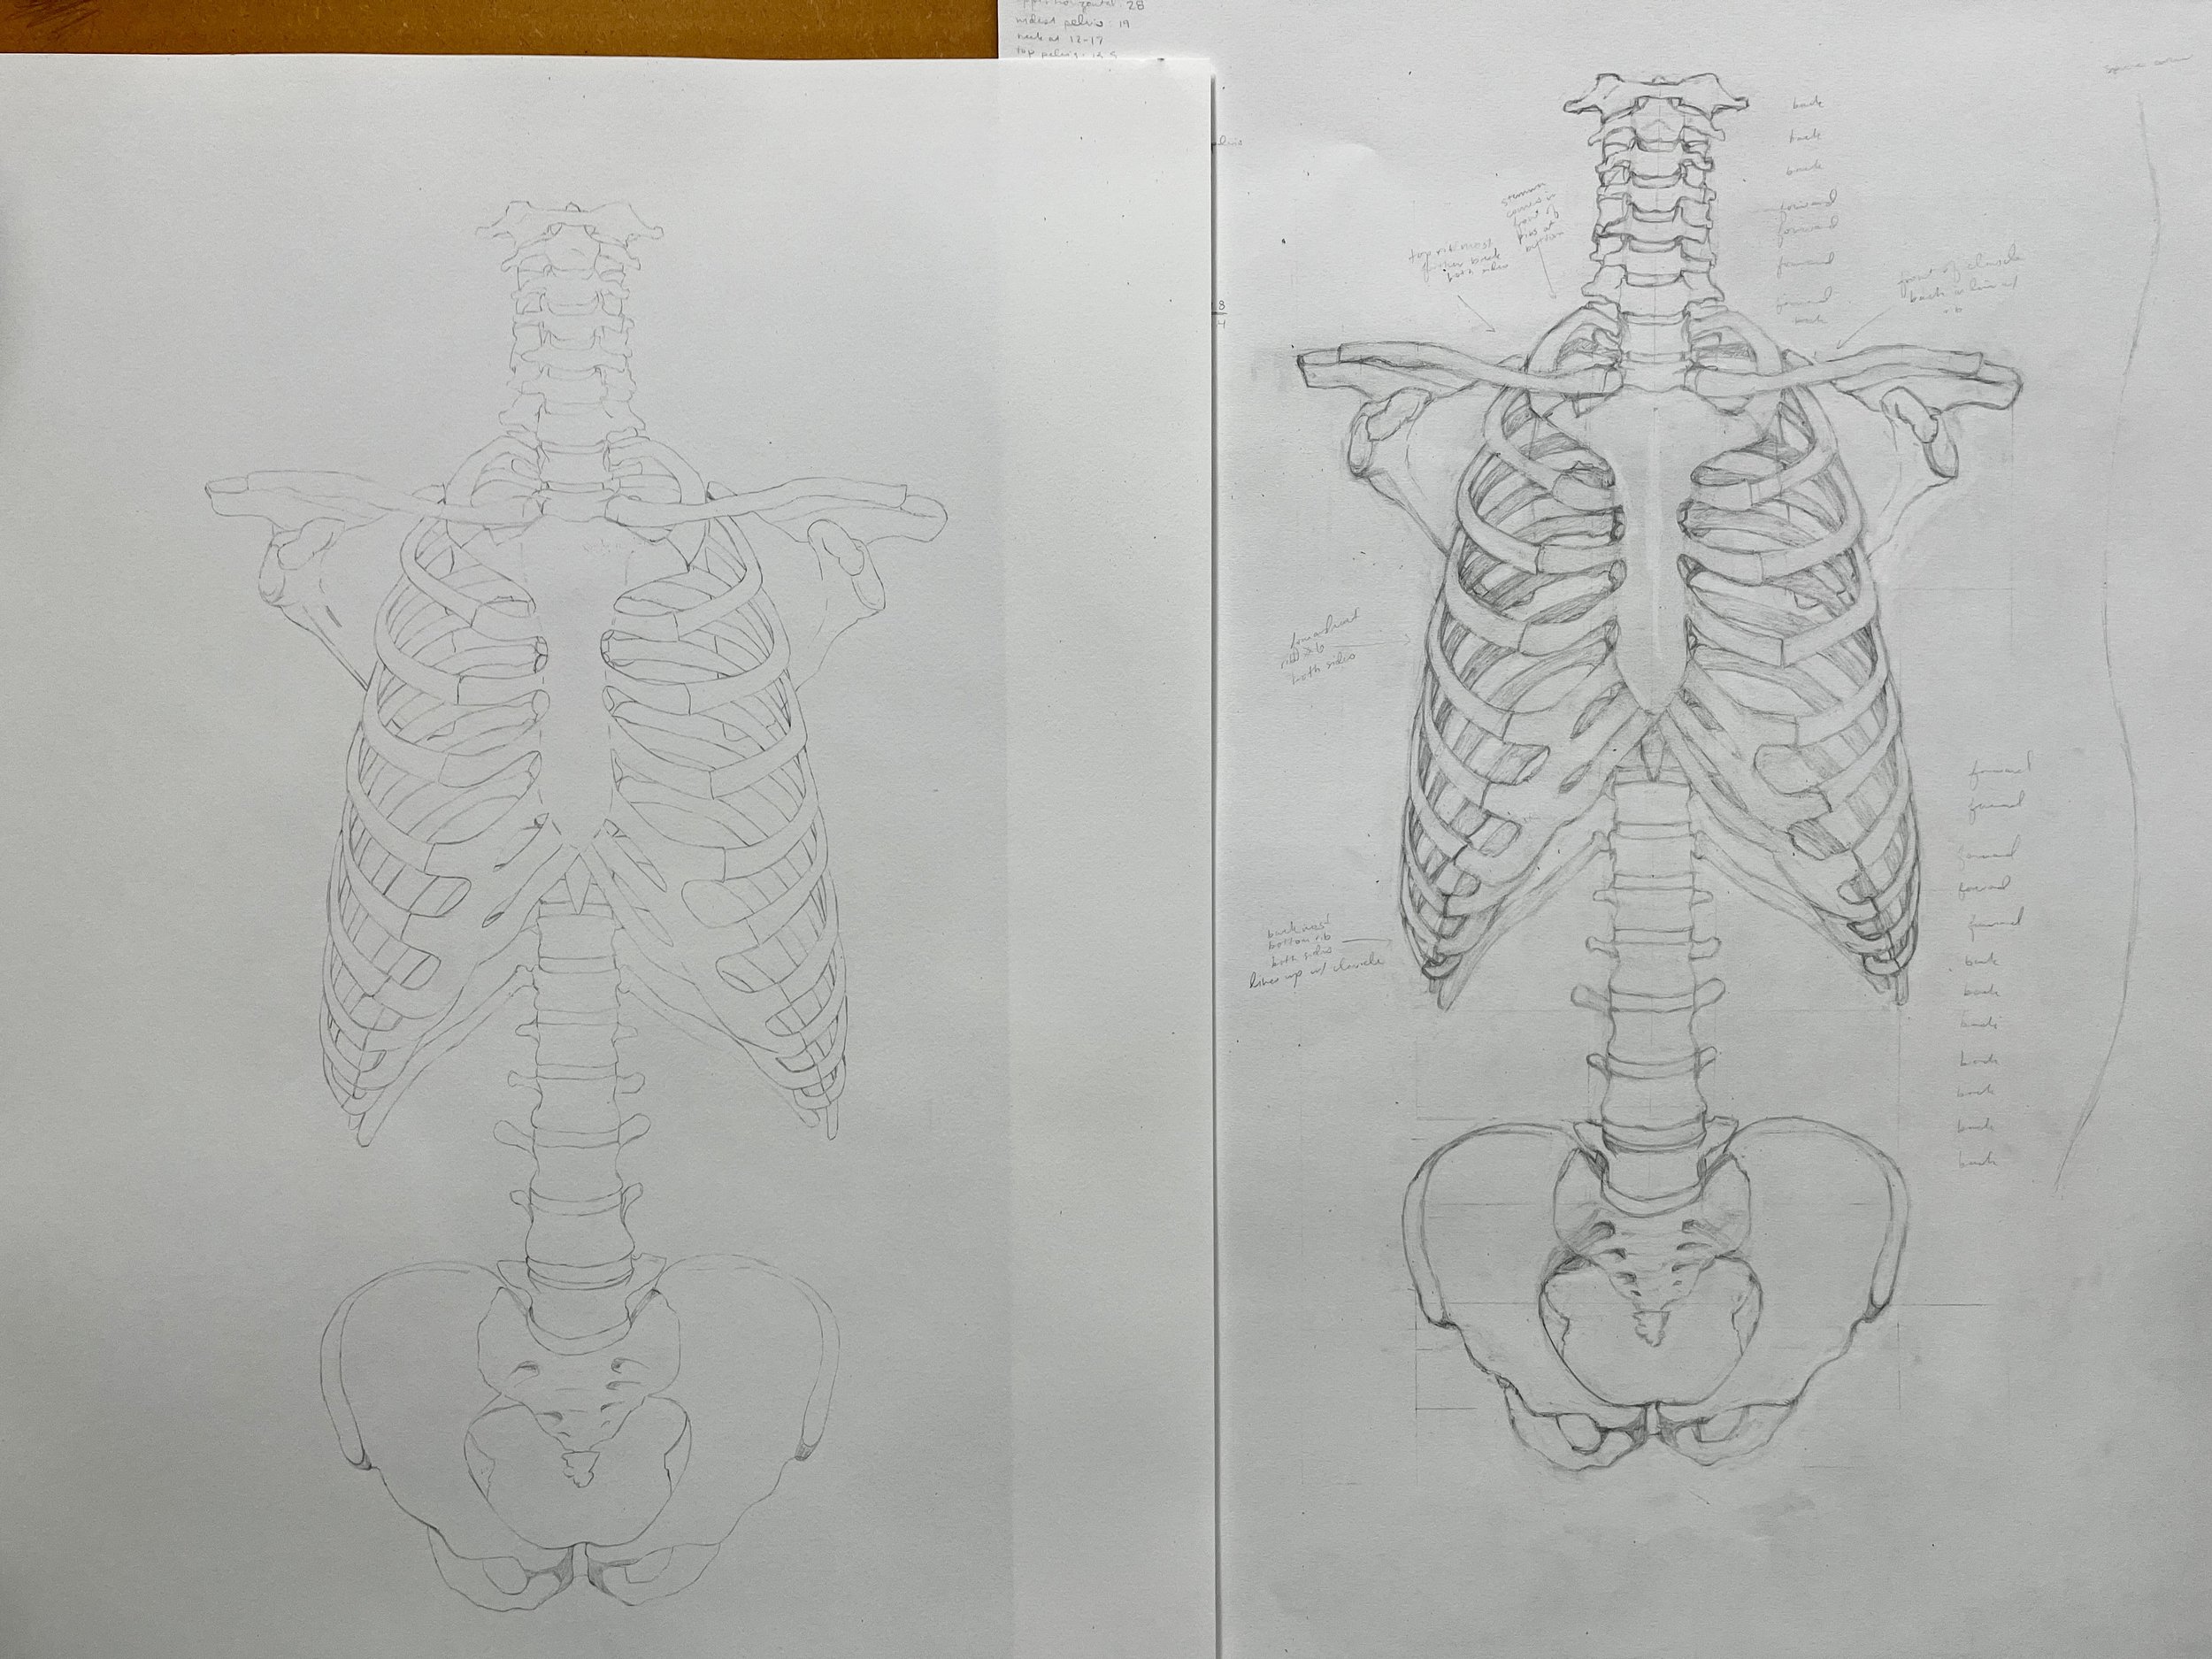

“Torso - Thoracic Cage, Vertebral Column, and Pelvis”

Overview:

Explored by means of observation, measuring, and drawing the structural interdependency of the human thorax, abdomen and pelvis. Drew a ventral view of the skeleton of a human torso (vertebral column, thorax and pelvis), the scapula, and clavicula, as detailed as possible at 1:1 scale. Added the appropriate nomenclature.

Form and negative space, proportions, simple foreshortening perspective, precise drawing technique

Final Product:

Medical textbook figure for medical students - graphite